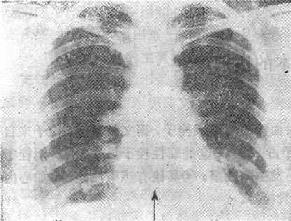

图116-1 肺梗死 三、肺动脉造影和数字减影血管造影 (一)数字减影血管造影(DSA)目前一般采用时间减影法。在注射造影剂前后将受检部位的影象由模数转换器转变成数据,输入计算机,指令造影后减去造影前,再由数模转换器转变成图象,通过显示和照象系统形成影象(纯血管影象)。应用简单周围静脉注射可能显示为非选择的,通过导管亦可做选择性的肺血管造影,肺血管的显示更为清楚。 (二)传统的肺血管造影 传统的肺血管造影是将导管从周围静脉插入,经右心至肺动脉系统,同时可做肺动脉压、血气分析等测量。造影是高压注射下快速连续摄片,可做选择性造影,根据肺片、肺扫描所见确定选择的部位。 (三)肺栓塞的血管造影表现 1.血管管腔内充盈缺损是肺动脉内栓子造成的直接征象,对诊断最有意义。 2.肺动脉完全阻塞造成的截断现象为诊断肺栓塞的可靠依据。 3.某一区域肺血管减少,可表现出“剪枝征”,像一树枝被剪掉样。 4.肺血管分布不均称,不完全阻塞时可以出现。 肺血管造影对肺栓塞的诊断具有很高的特异性,并且可进一步进行溶栓治疗(介入放射学),但是它是一种损伤性检查方法,可以出现并发症。 四、放射学诊断方法的选择原则 临床上症状(胸痛、呼吸困难、咯血)、体征(呼吸急促、肺动脉第二音亢进、发绀)、血气分析(低氧血症)等怀疑肺栓塞的可能,依下列原则选择放射学诊断方法。 1.首先选择胸部平片,可除外其他原因引起的上述临床表现,且有时能发现诊断肺栓塞的依据。 2.肺的通气和灌注扫描为第2位影象诊断方法,有一部分病人可以除外或肯定肺栓塞的诊断,而终止检查。 3.对于临床、X线及肺扫描均不能明确诊断而又非常怀疑则应考虑数字减影肺血管造影或传统的肺血管造影检查。